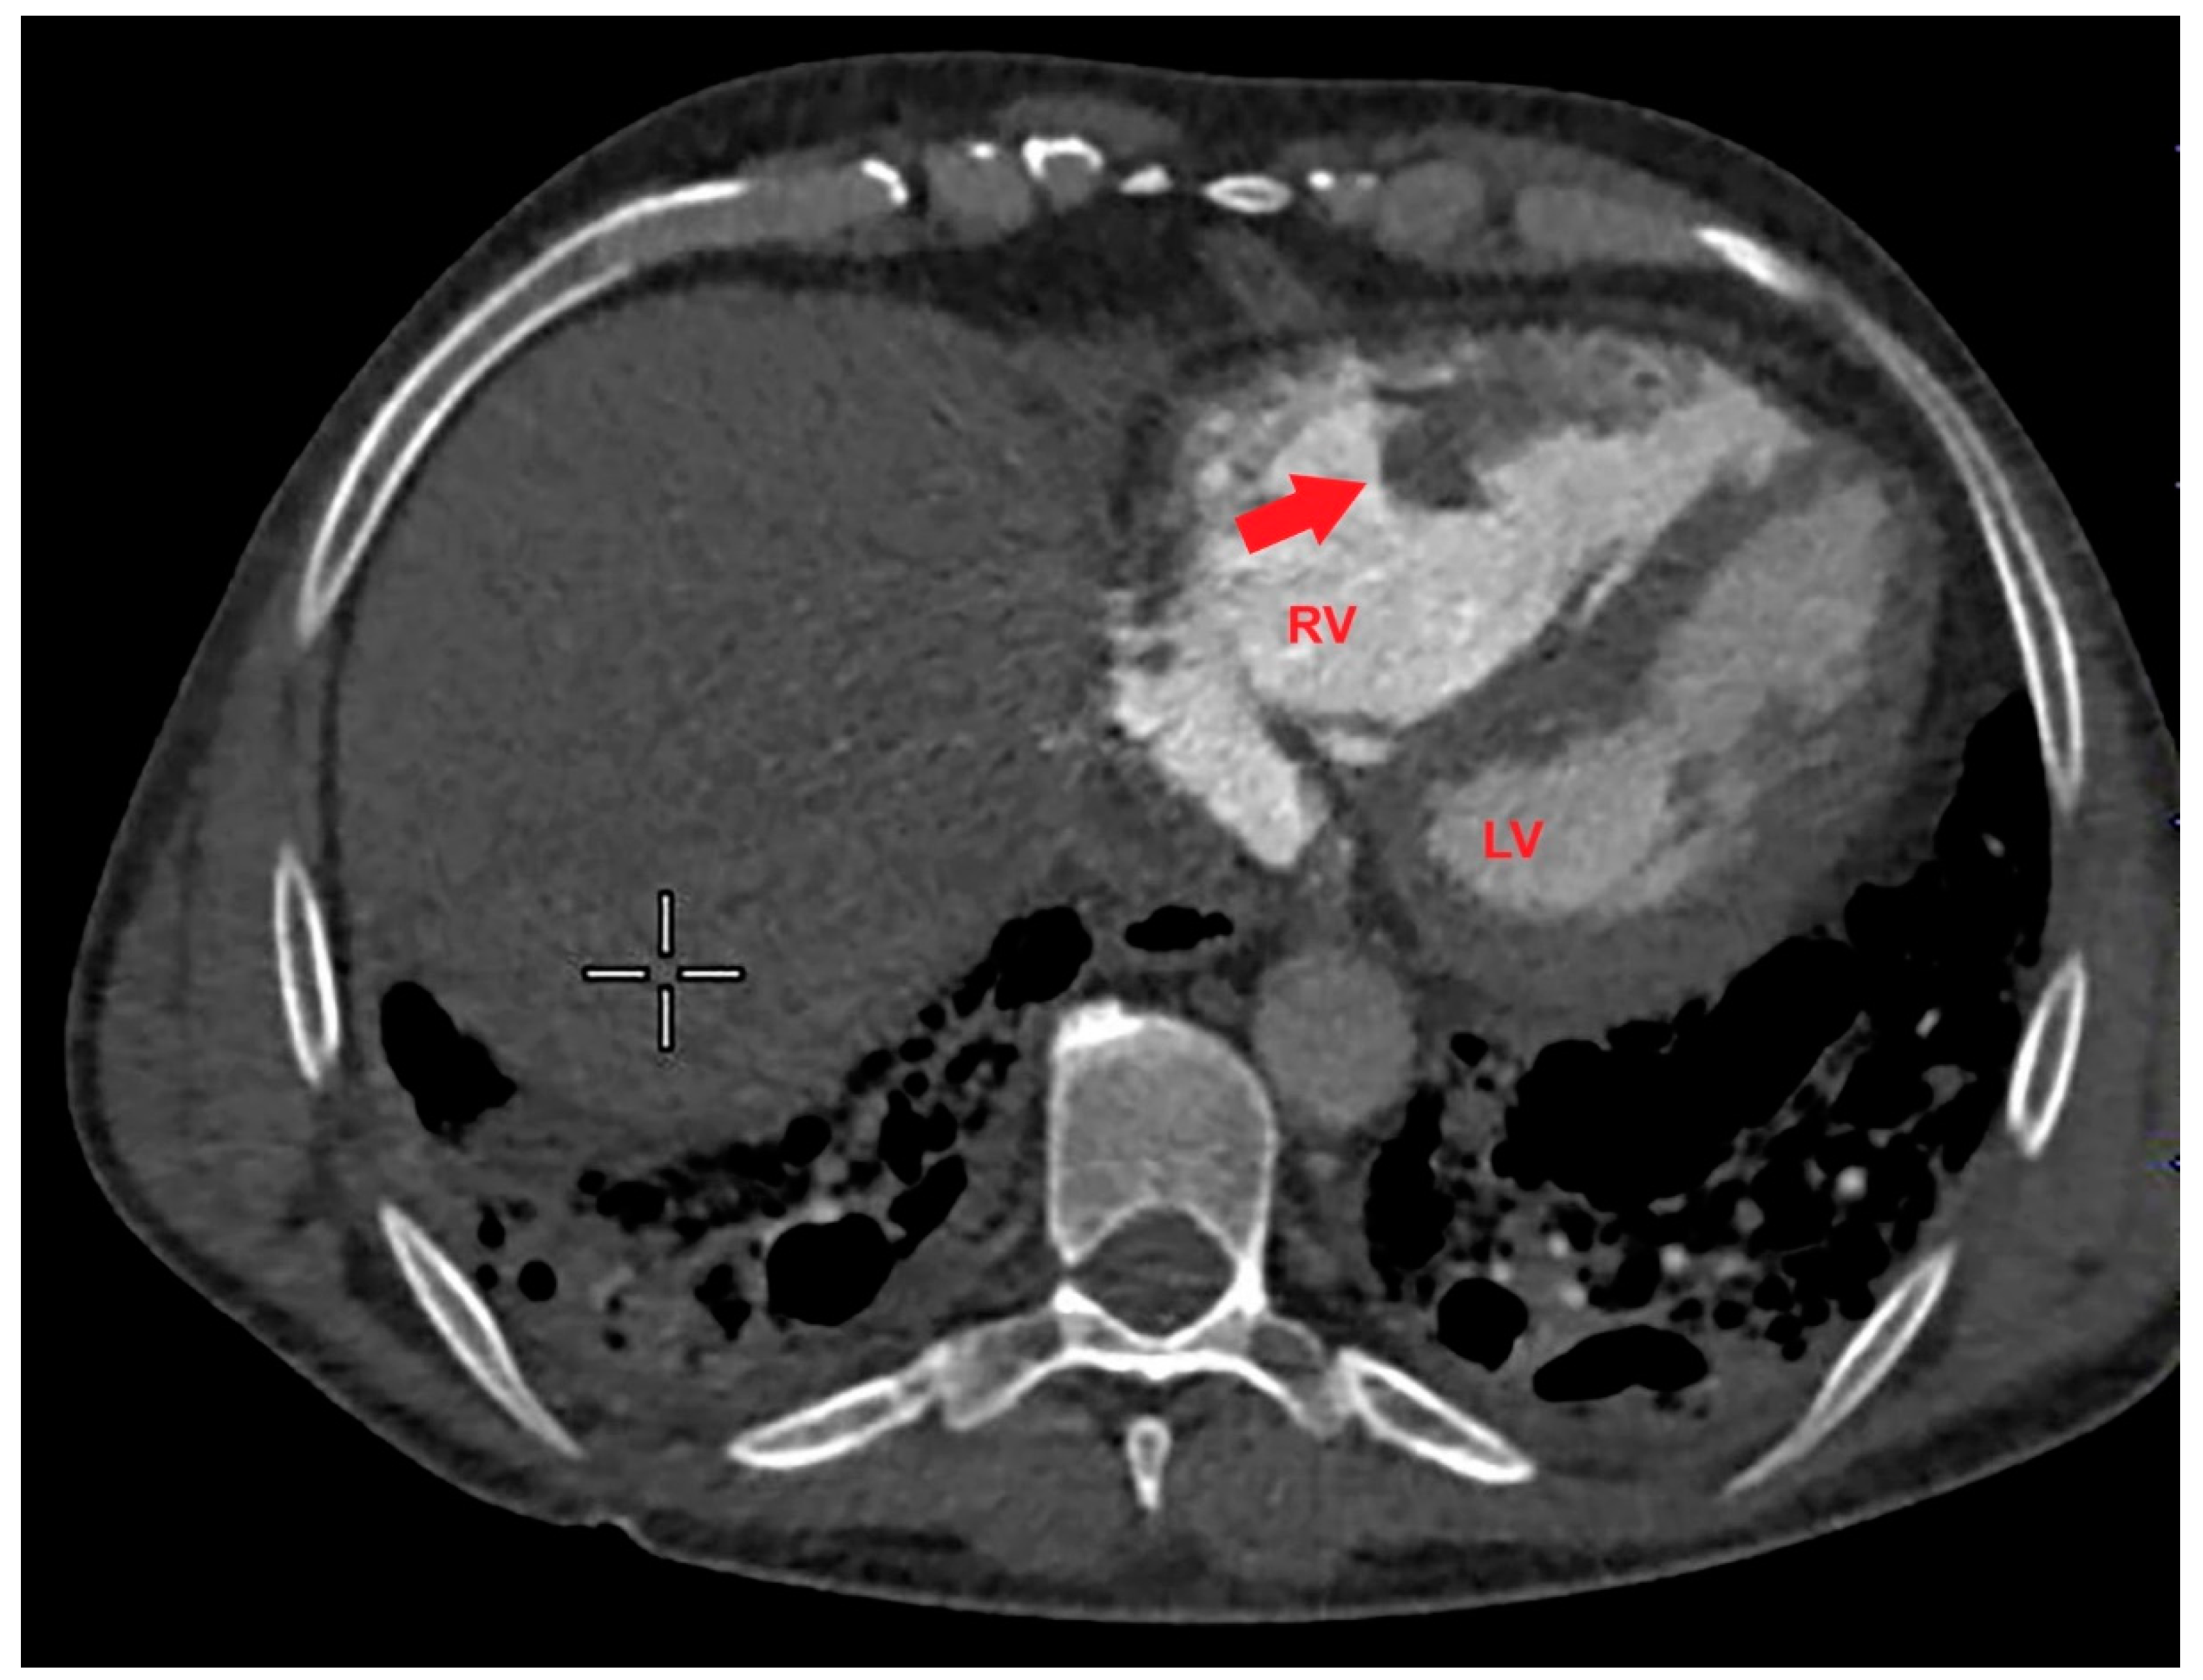

Based on the ECG and echocardiographic findings and the complex patient’s history, the pulmonologist suggested a diagnostic study with contrast-enhanced chest CT. The examination confirmed severe RV dilatation with a large filling defect involving the mid-apical region of the right ventricle (Figure 4).

Figure 4. Axial contrast-enhanced chest computed tomography showing a large filling defect (red arrow) involving the mid-apical region of the right ventricle. LV, left ventricle; RV, right ventricle.